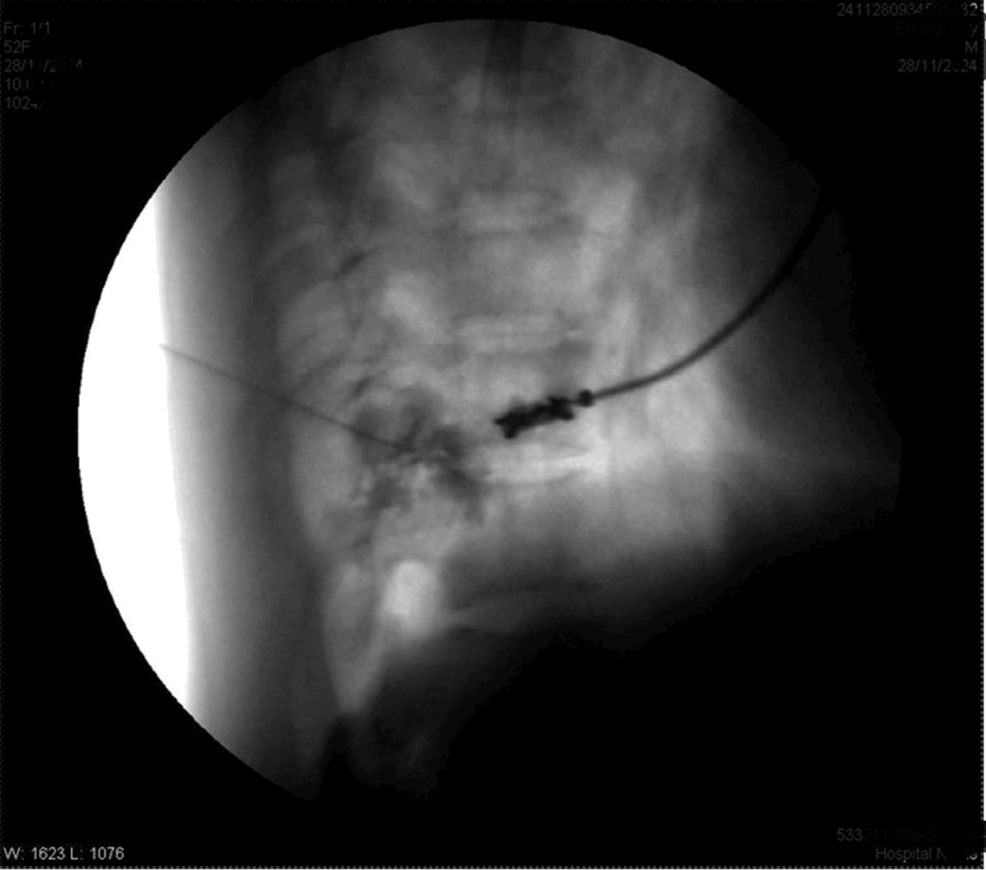

The patient was positioned prone. After painting and draping, the transverse process of T8 was located on the right side with the help of a C-arm. A Quincke needle (22 G) was inserted under fluoroscopic guidance to reach the transverse process of T8. The needle tip was advanced caudally along the transverse process until a loss of resistance was felt. The needle’s position was confirmed via fluoroscopy by injecting iohexol 300 radiocontrast dye, with images obtained in both anteroposterior and lateral views (Figures 1–4).

Four milliliters of levobupivacaine 0.5% were administered. Similar steps were performed for the T10 and T12 vertebrae. Sensory levels were assessed using hot and cold glass test tubes along the mid-axillary line. Motor blockade was evaluated using Snider’s match-blowing test, where the patient was asked to blow out a match held 15 cm from the mouth. Vitals after five minutes were HR of 90/min, BP of 100/68 mmHg, SpO2 of 98%, and RR of 14/min.